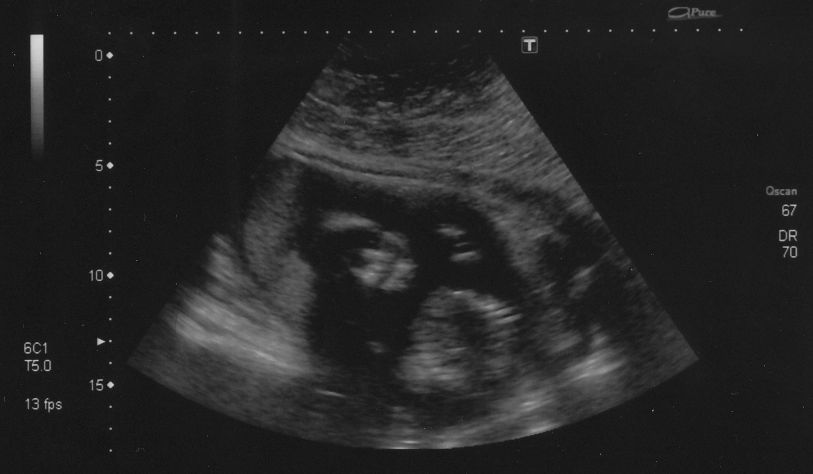

Danyoo wrote:The technician was having a hard time getting measurements because Cody was so active. "If I could just get baby to stop moving for a tenth of a second...I could measure his femur!"